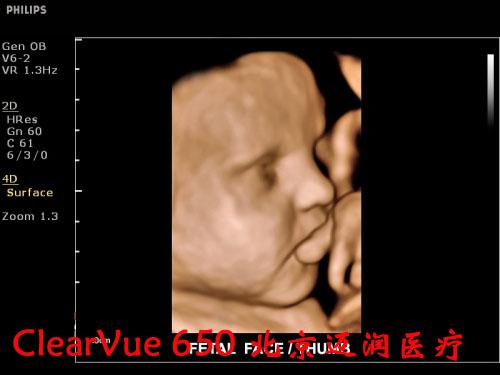

對實時三維功能而言,CV650是飛利浦CV系列產(chǎn)品“維時代”的開端。

良好的二維成像技術(shù)是保證實時三維圖像質(zhì)量的關(guān)鍵。CV650的實時三維成像融合了飛利浦傳統(tǒng)的優(yōu)勢技術(shù)SONOCT和Xres,保證了良好的圖像分辨力和對比度;另外,容積探頭也采用了“雙A探頭技術(shù)”,能夠?qū)崿F(xiàn)原始信號的零損耗,使呈現(xiàn)的三維圖像效果更逼真。同時,高速的處理內(nèi)核能使容積探頭實現(xiàn)最大48幁/秒的掃描速率,完成一次靜態(tài)掃描的時間也只需要2秒鐘,這些都保證了容積成像的可操作性。

在實時三維應(yīng)用上,CV650配備了胎兒面部自動識別軟件,全新的胎兒面部信息數(shù)字鑒定技術(shù),能夠一鍵清除遮擋物,使胎兒面部結(jié)構(gòu)尤其是異常缺陷能夠瞬間清晰顯示,大大便捷了醫(yī)生對胎兒面部的掃查過程。鑒于基層醫(yī)院對于胎兒心臟先天性疾病診斷能力的不足,這款機器還配備有STIC成像功能,簡單的操作、快速的圖像獲取、強大的離線分析能夠保證準確高效地獲取胎心不同標準切面,是基層超聲醫(yī)生診斷胎兒先心病的利器。

飛利浦ClearVue 650超聲系統(tǒng)臨床高清圖片